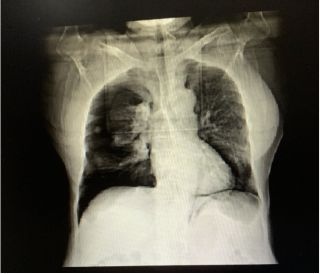

次日复查X光片,提示:

1、双侧气胸术后:右下胸腔肺野透亮度增高,待排少数气胸残留。

2、考虑双肺散在炎症。